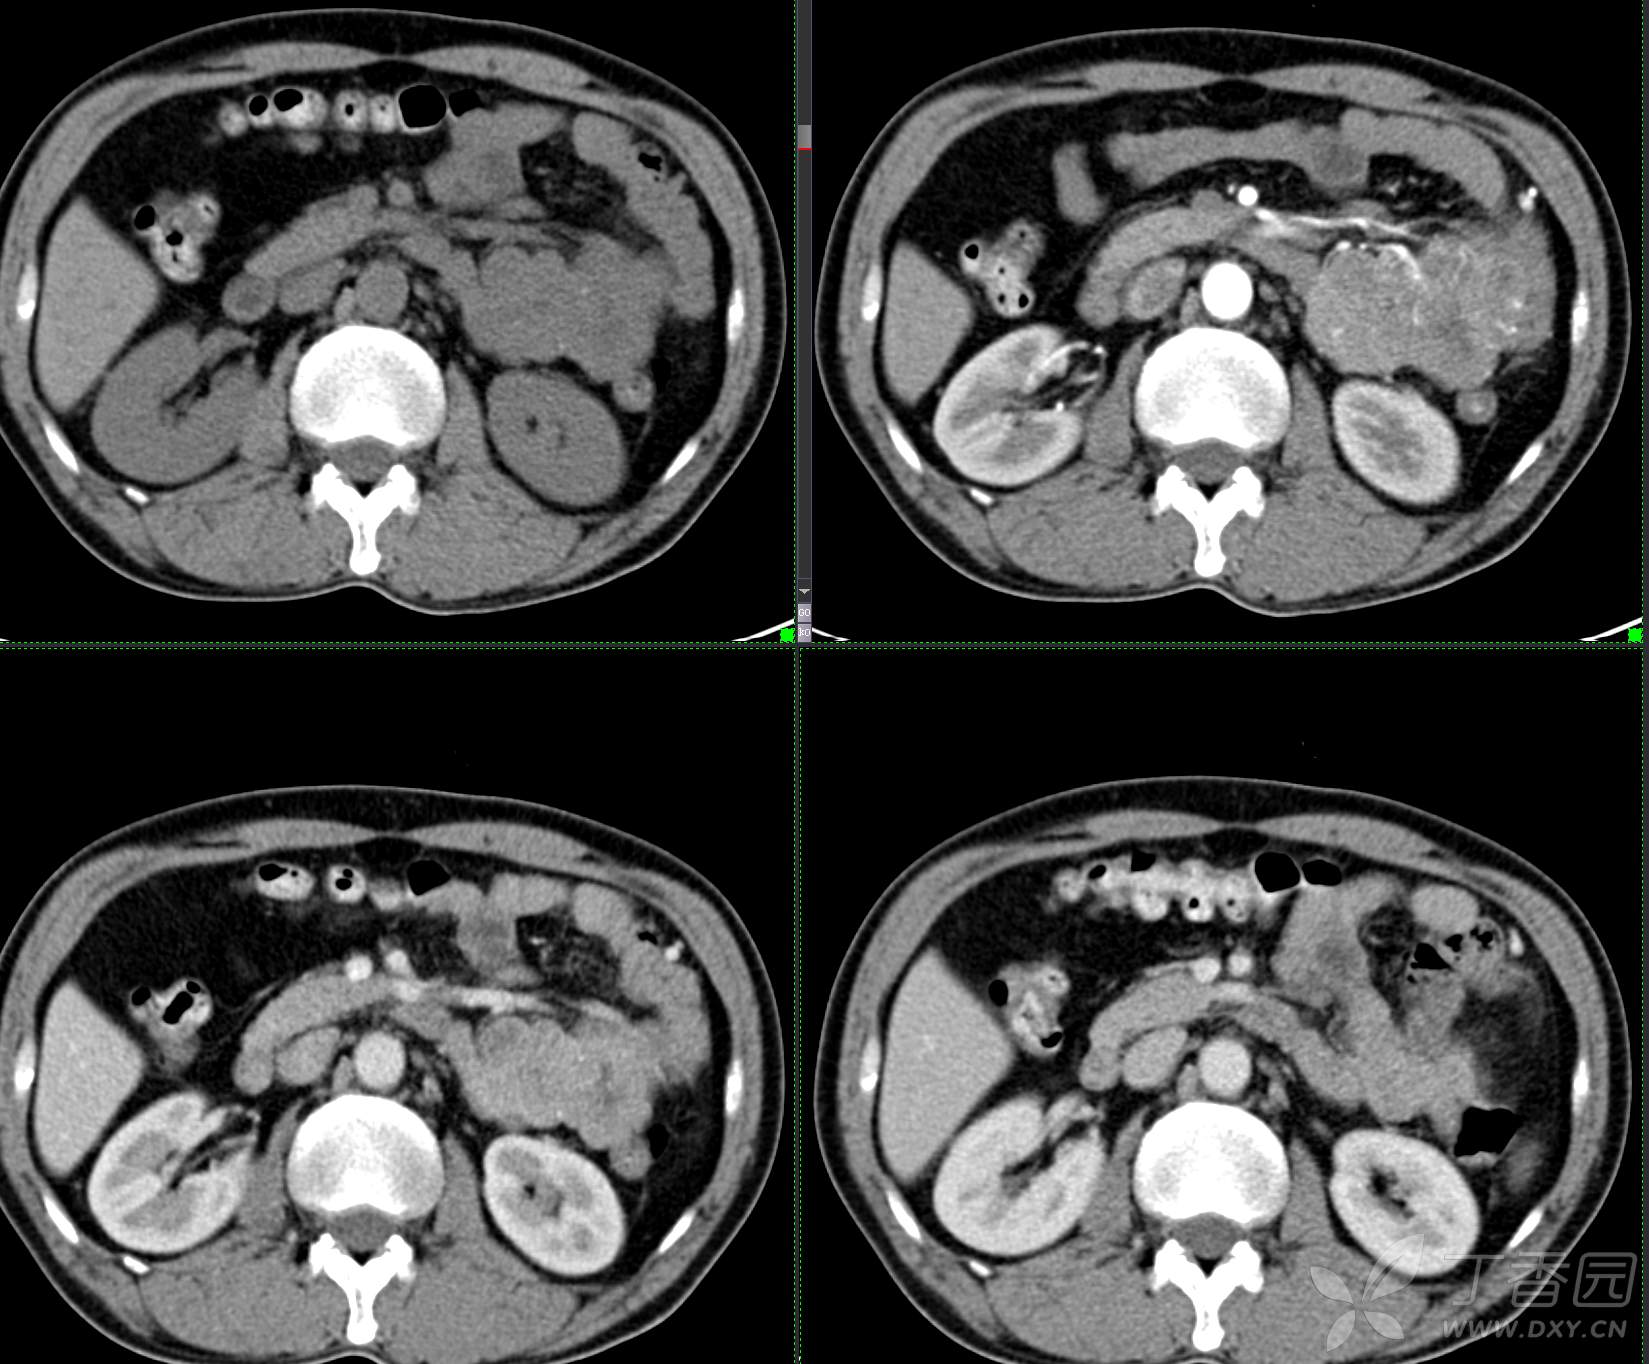

讨论:小肠病变,间质瘤?淋巴瘤?小肠腺癌?